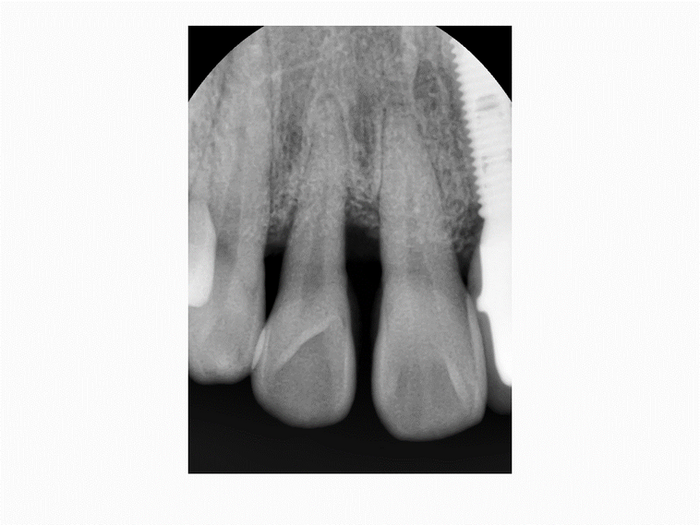

1. Surgery: #21 Bone Graft